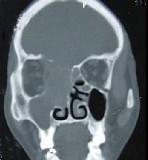

问题 女性,53岁,右侧鼻腔流血近1年,近来头痛,行CT检查如图所示,请选择正确的答案()

选项 A.鼻腔癌 B.鼻腔内息肉 C.副鼻窦炎 D.鼻腔炎性假瘤 E.鼻腔内血管瘤

答案 A